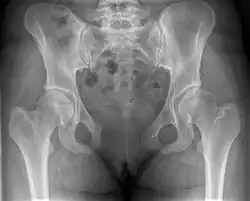

Pubic symphysis diastasis

Pubic symphysis diastasis (also known as diastasis symphysis pubis) is the separation of normally joined pubic bones, as in the dislocation of the bones, without a fracture that measures radiologically more than 10 mm. Separation of the symphysis pubis is a rare pathology associated with childbirth and has an incidence of 1 in 300 to 1 in 30,000 births. It is usually noticed after delivery but can be observed up to six months postpartum.[1] Risk factors associated with this injury include cephalopelvic disproportion, rapid second stage of labor, epidural anesthesia, severe abduction of the thighs during delivery, or previous trauma to the pelvis. Common signs and symptoms include symphyseal pain aggravated by weight-bearing and walking, a waddling gait, pubic tenderness, and a palpable interpubic gap. Treatment for pubic symphysis diastasis is largely conservative, with treatment modalities including pelvic bracing, bed rest, analgesia, physical therapy, and in some severe cases, surgery.[2]

This abnormally wide gap can be diagnosed by radiologic studies such as X-ray, Ultrasound, MRI, CT scan or bone scan. While X-Ray is the gold standard to identify a separation of the pubic symphysis, a decision must be made in regard to which imaging modality to utilize that is patient and case-specific.[3]

X-ray

An X-ray film obtained in the AP view of the pelvic inlet and outlet will show a marked gap between the pubic bones.[3] A normal pelvis will show a gap that is 4–5 mm. However, in pregnancy the hormonal influences cause relaxation of the connecting ligaments and the bones separate up to 9 mm. A gap measuring greater than 10 mm indicates a pathological process.[3]

In addition, a view in the "flamingo stance" can be obtained to demonstrate the instability of the joint. This position consists of the patient standing with weight on one leg and the other bent.[6] A vertical displacement of more than 1 cm is an indicator of symphysis pubis instability.[7] A displacement of more than 2 cm usually indicates involvement of the sacroiliac joints.[3]